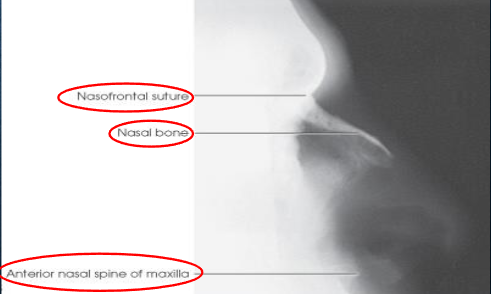

Lateral nasal bones

patient position:

upright or recumbent anterior oblique position

MSP parallel with IR

part position:

IPL perpendicular

flex neck to place IOML parallel to transverse axis of IR

respiration suspended

CR:

perpendicular

enters 1 inch distal to nasion

collimation:

extends from the glabella to 1 inch inferior to the acanthion and ½ inch beyond the tip of the nose

should be no larger than 3 × 3 inches

both sides done for comparison

Lateral nasal bones image criteria

shows:

nasal bone and soft tissues of the nose

anterior nasal spine

frontonasal suture

no rotation